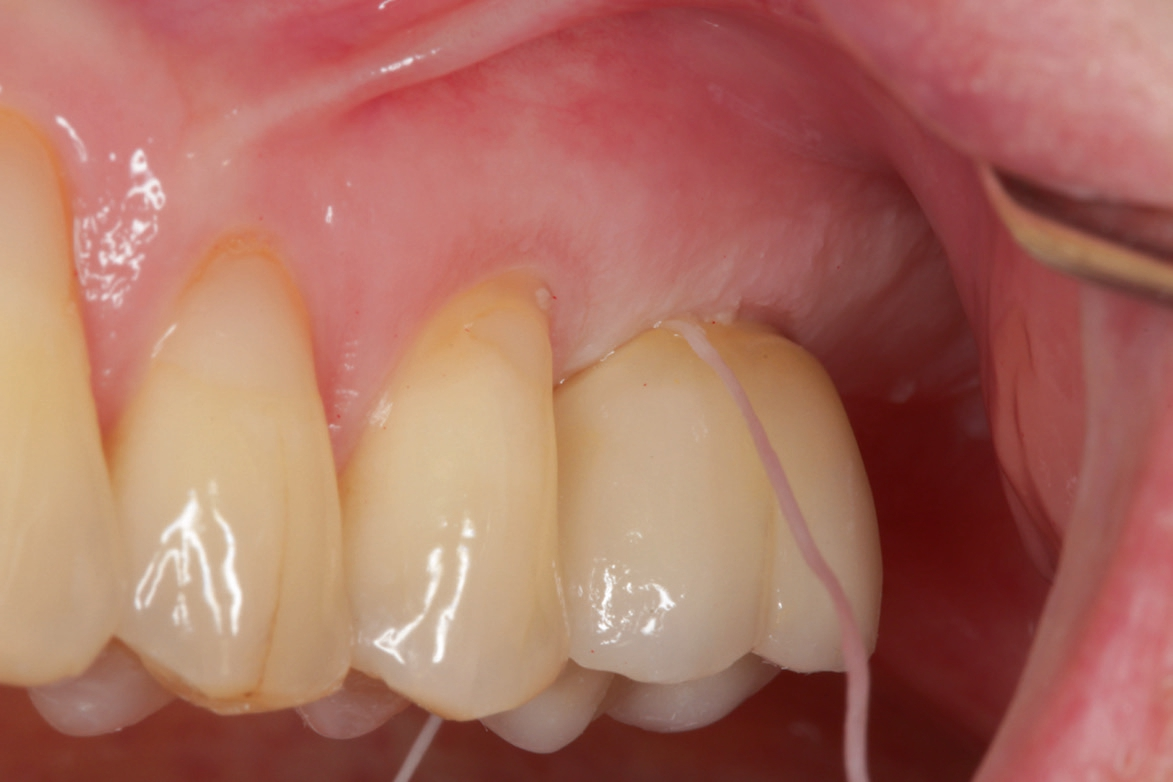

Vor Eingliederung der Krone wird die Hygienefähigkeit geprüft und sichergestellt, dass zukünftig in Okklusion und Artikulation keine traumatischen Kräfte auf die Restauration wirken. Nach Anziehen des erforderlichen Drehmoments wird der Schraubenkanal mit Teflonband gefüllt und ein okklusaler Verschluss mit Komposit vorgenommen.